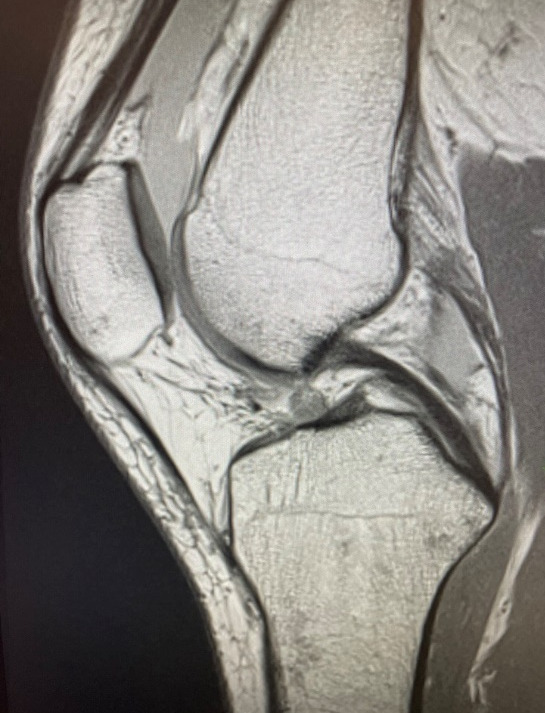

A 25-year-old female fell while skiing and suffered a twisting injury to her right knee. MRI confirmed a complete rupture of her ACL (Figure 1), as indicated by the high intensity signal at the site of injury. She was scheduled to undergo ACL reconstruction. The patient, an avid soccer player as well as a high-level skier, works with children and kneels often in her daily life; she expressed concern that a BTB graft may lead to anterior knee pain post-operatively. As a result, the decision was made to use a hamstring autograft. Part of the pre-operative discussion centered around the fact that hamstring autograft size is highly variable. Thus, it was determined that augmenting the hamstring graft with a 5 x 250 mm BioBrace implant was a viable option if the graft was undersized upon harvest.